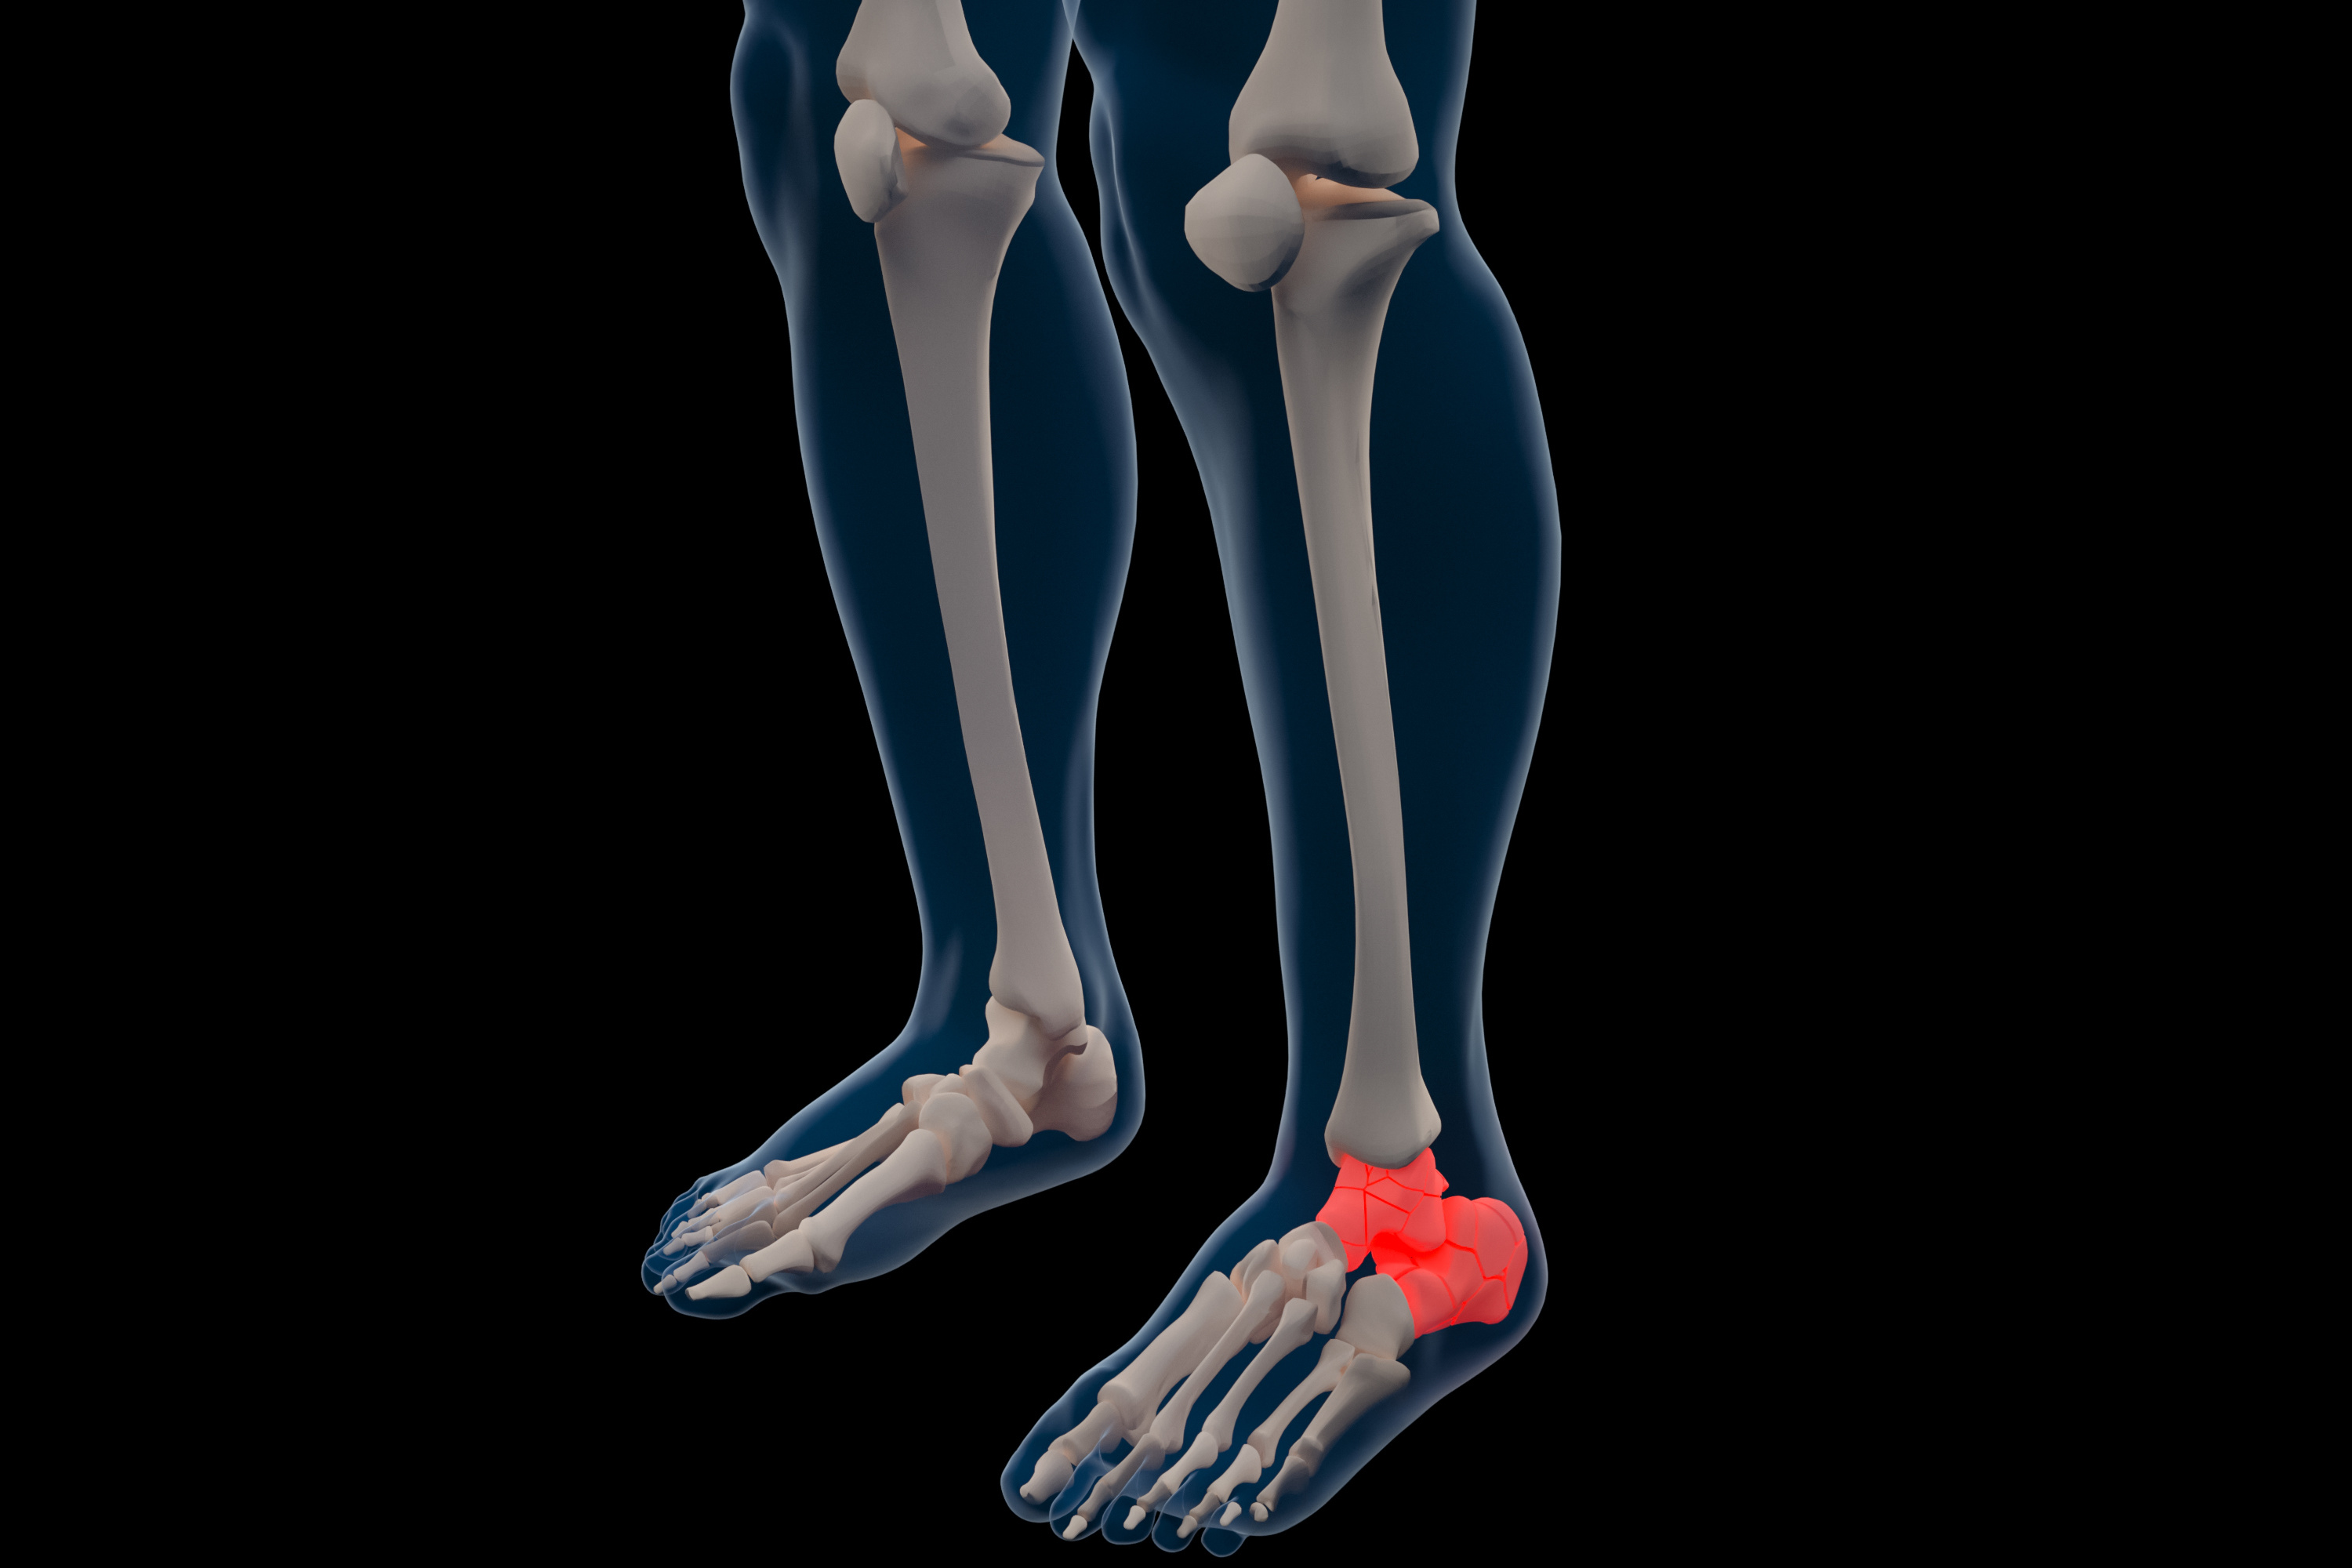

干货:德国医生跟骨骨折手术治疗技巧分享!

跟骨骨折微创置钉治疗技术,实操病例讲解!